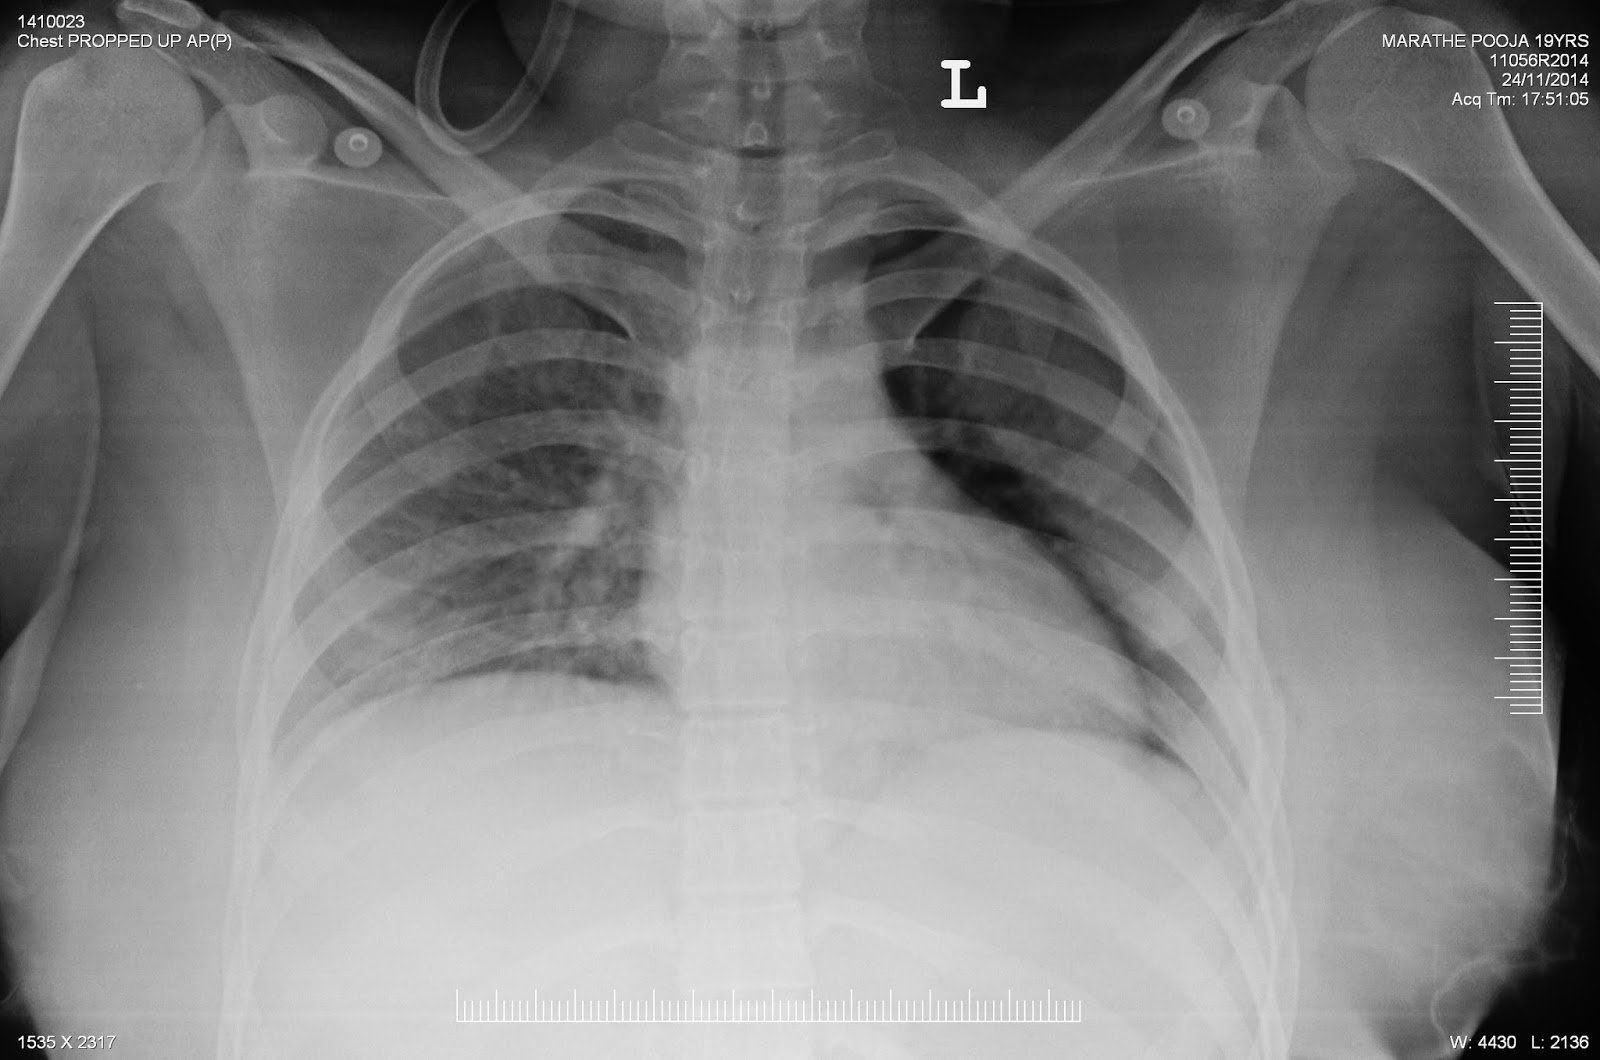

An elderly person accidentally ate a tablet along with its foil followed by severe chest pain.

There was a esopahegal tear with leak into the right pleural space. It was managed conservatively. After 1 month he developed right sided empyema. So the tear was sealed by a plugging device. Gastrograffin swallow done after the procedure did not reveal any leak.